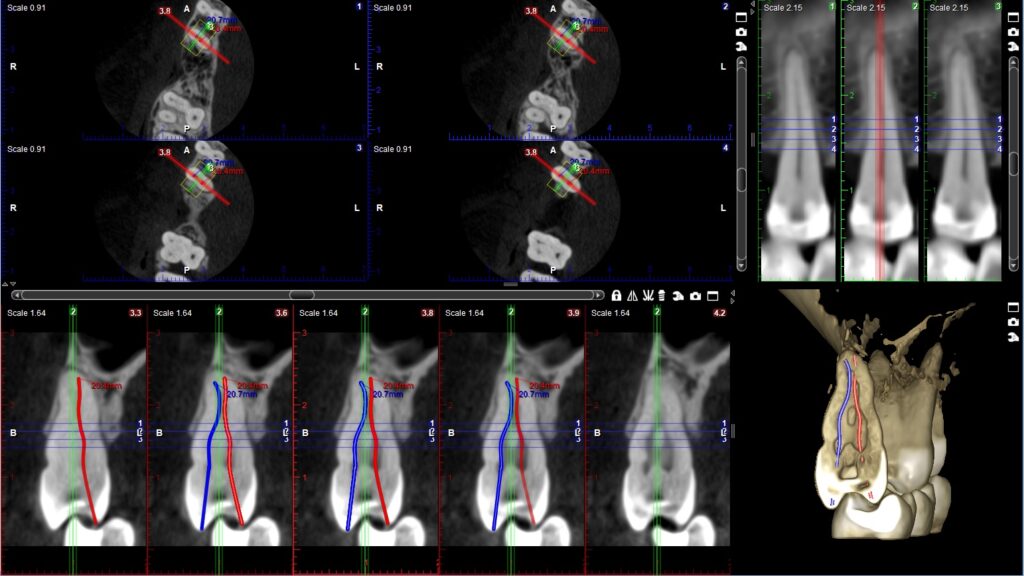

05. Endodoncija

Primena CBCT snimka u oblasti endodoncije:

• Procena komplikacija endodontskog lečenja

• Dg periapikalne patologije

• Komplikovan sistem kanala korena

• Utvrđivanje zakrivljenosti kanala korena

• Dg traume – fraktura korena, alveolarnog nastavka, luksacije

• Lokalizacija resorpcije korena

• Određivanje tačne lokalizacije apexa korena u prehirurškom planiranju

• Tačne mere